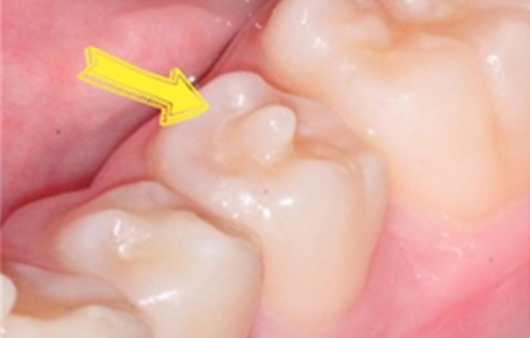

종종 치아에 뿔처럼 작은 돌기가 나 있는 경우가 있는데, 이를 치아에 작은 치아가 나와 있다고 해서 '치외치(Dens Evaginatus)'라고 합니다.

종종 치아에 뿔처럼 작은 돌기가 나 있는 경우가 있는데, 이를 치아에 작은 치아가 나와 있다고 해서 ‘치외치(Dens Evaginatus)’라고 합니다. 치외치는 가장 흔한 기형 치아로 하악소구치에 많이 생기고 유전적인 영향이 많다고 알려져 있습니다.

교합면 가운데에 치외치가 생기면 볼록 튀어나온 부분이 맞물리는 대합치와 교합 시 씹히면서 지속적인 충격을 받아 치아가 마모되거나 파절될 수 있습니다. 그럴 경우 치외치 내에 신경이 따라 올라와 있기 때문에 신경이 노출되고, 충치가 없는데도 불구하고 치아의 신경이 괴사하여 고름이 생기거나 통증을 유발하게 됩니다.